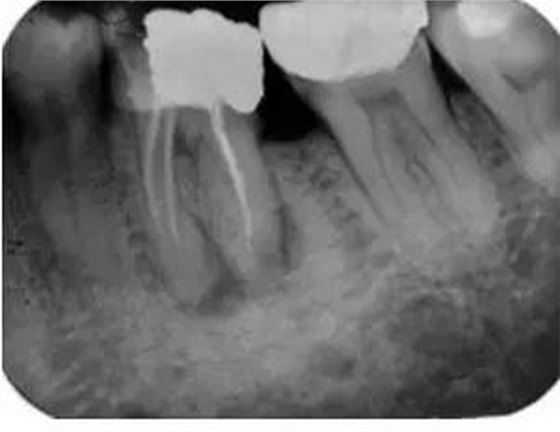

如果根管內(nèi)有樁、折斷的器械或根充物,那么該患牙的治療難度就會(huì)增加(圖3)。樁能否從根管內(nèi)取出取決于樁的大小和形態(tài)。如果根管內(nèi)的折斷的器械位于根尖三分之一和彎曲根的根方,將折斷器械取出來(lái)的難度要比在冠方的更困難。